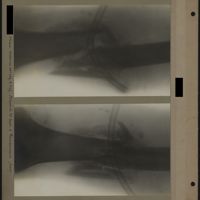

0007 - Page 3 - [Radiographies du bras]0007 - Page 3 - [Radiographies du bras]